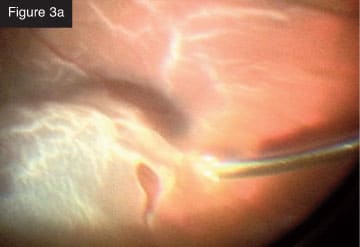

Membrane removal with vitrector. CASE 3: Total rhegmatogenous retinal detachment. I frequently combine scleral buckling with small-gauge vitrectomy. In a recent case of total rhegmatogenous retinal detachment (Figures 3a and 3b), I first did the scleral buckle and then removed the vitreous from the periphery with minimal traction on the retina. The creation of iatrogenic breaks is markedly reduced with this technology. I injected perfluorocarbon liquid and aspirated subretinal fluid. I like to aspirate often with the vitrectomy probe through the break. Next, I applied laser photocoagulation to the break. With the flexible tip laser probe, I find I can treat that entire area in an elegant, quick way, even in phakic

Rhegmatogenous retinal detachment.